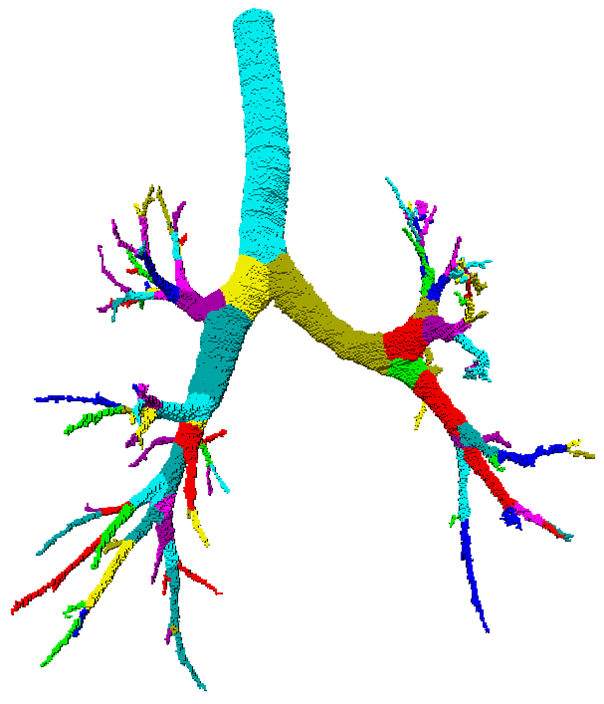

Segmentation - adaptive region growing (left), extracting centerlines - topologically and geometrically correct thinning (middle), and excluding branch-areas based on 3D distance map calculation (right).

Partitioning centerlines in a formal tree data structure (left), partitioning segmented tree via isotropic label propagation (middle), and quantitative analysis formal XML tree with associated measurements (right).